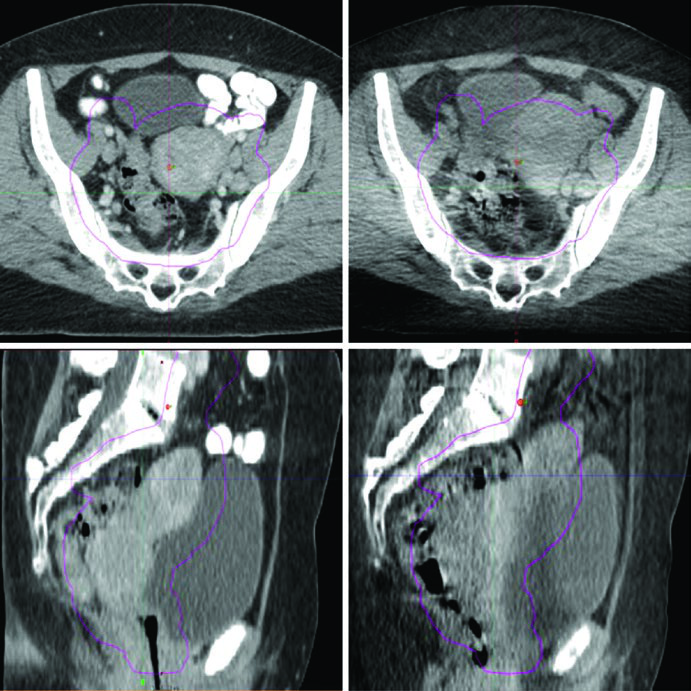

- Cone-beam CT (CBCT) diário: permite identificar o estado de enchimento retal e vesical em comparação à simulação. Com expansão de PTV baseada em modelo de forma e guia diário por CBCT, a cobertura do alvo dentro da isodose de 95% demonstra-se excelente.

- Monitoramento da variação: a Figura 24.1 ilustra um caso real em que mudanças no enchimento vesical e retal deslocaram o fundo uterino para fora do PTV — exatamente o tipo de evento que o CBCT pré-tratamento detecta e permite corrigir.

Na prática diária, o CBCT oferece o melhor equilíbrio entre informação anatômica e viabilidade logística. A dose adicional de imagem é clinicamente aceitável quando comparada ao risco de subdosagem tumoral por deslocamento não detectado.